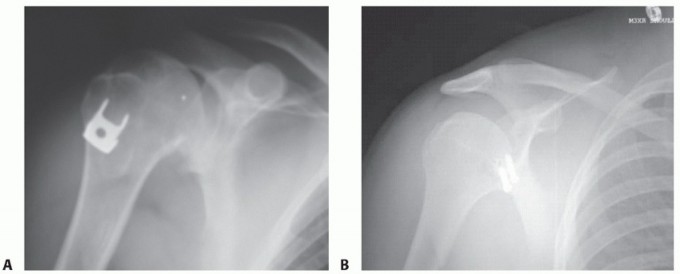

Radiographs include anteroposterior (AP), lateral, and axillary views (FIG 3A,B). The axillary view is particularly important for assessing anterior glenoid rim defects.

* FIG 3 • AP radiographs of the left shoulder showing a dislocated shoulder (A) and subsequent reduction

(B). There is a Hill-Sachs fracture of the posterolateral humeral head. C. Axial MRI scan in a patient with deficient glenoid labrum and subscapularis tendon tear.